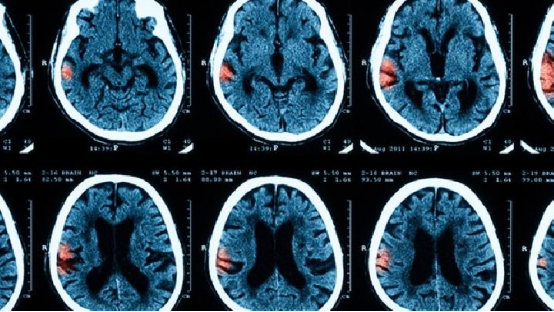

"这些年轻人的大脑正在经历'三重绞杀':β淀粉样蛋白沉积、tau蛋白过度磷酸化、神经突触连接断裂。"国家老年疾病临床医学研究中心专家指着小雨的脑部影像,语气凝重。